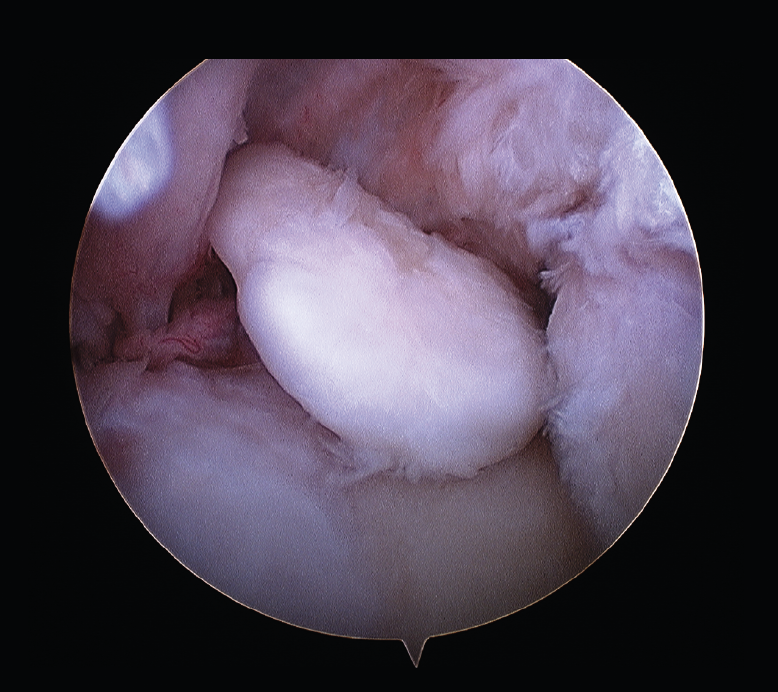

Las patologías más habituales tratadas por medio de una artrolisis artroscópica incluyen: la sinovectomía parcial, el desbridamiento intraarticular de adherencias o lesiones condrales y la liberación capsular y/o capsulotomía anterior y posterior. Los cuerpos libres se pueden extraer y también resecar los osteofitos, frecuentemente situados en coronoides, olécranon o en la foseta olecraneana humeral (Figura 4).

Figura 4. Exéresis de cuerpos libres articulares por artroscopia.

Los principales beneficios del método artroscópico son la agresión quirúrgica limitada, un inicio más precoz de la rehabilitación y la revisión detallada de la patología intraarticular. Este procedimiento es técnicamente exigente, precisa del uso de al menos 2 portales anterolaterales y mediales para abordar la cara anterior del codo (liberación capsular, limpieza de la fibrosis de la cabeza del radio, exéresis de cuerpos libres) y al menos 2 portales posteriores para trabajar en la foseta olecraneana, la parte posterior de la cabeza del radio y en la inserción del tríceps.